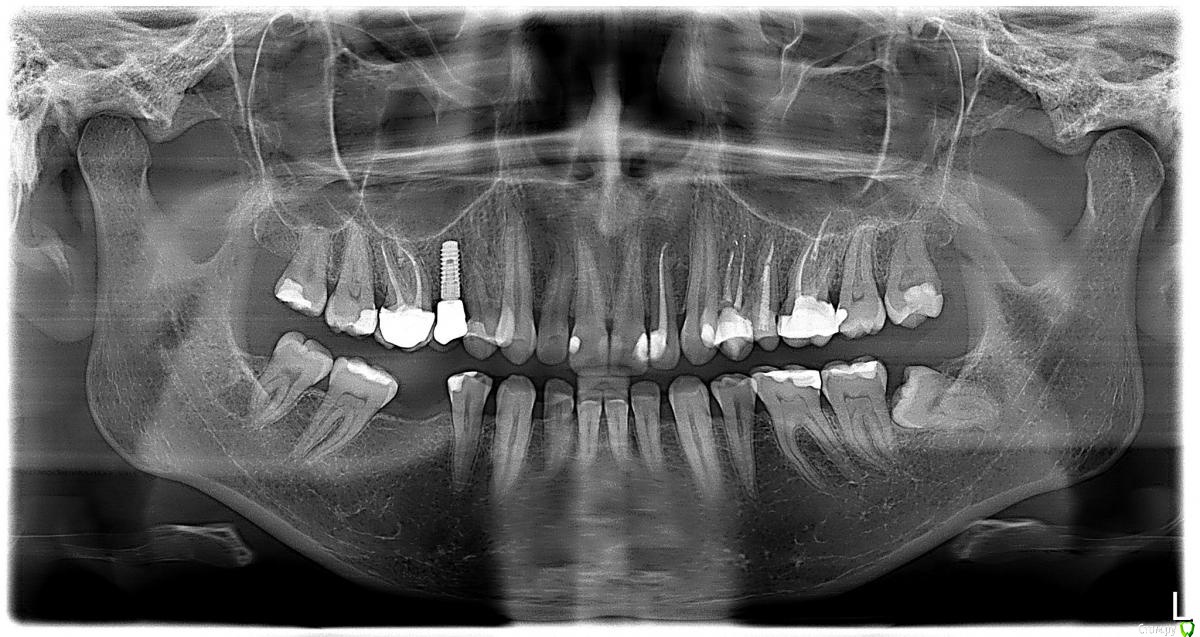

Miramar Опубликовано 28 июня, 2019 Автор Поделиться Опубликовано 28 июня, 2019 Вот пока панорамный снимок с неудалённой восьмёркой. Она у меня была слева сверху; на снимке, получается, справа. Фото пока не понимаю, с какого ракурса сделать. Ссылка на комментарий